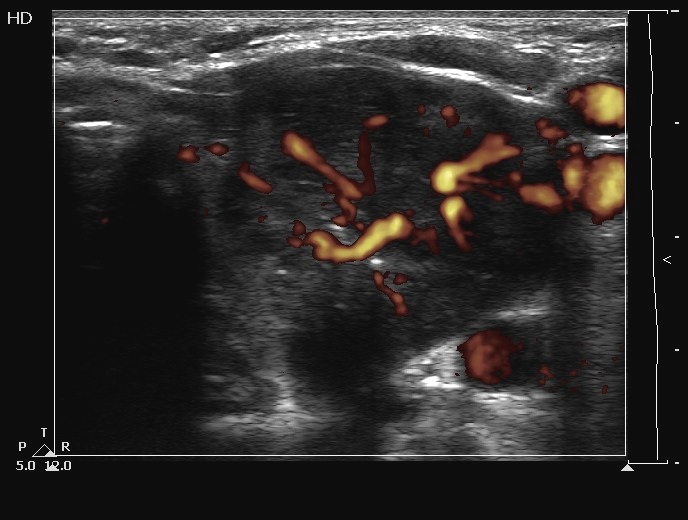

Ultrasonography. The thyroids were echonormal and contained several cystic areas and an echonormal nodule in the right lobe. There was a large partly echonormal, partly hypoechogenic nodule in the left thyroid. This lesion had irregular bordersr and presented an irregularly increased intranodular vascularization.